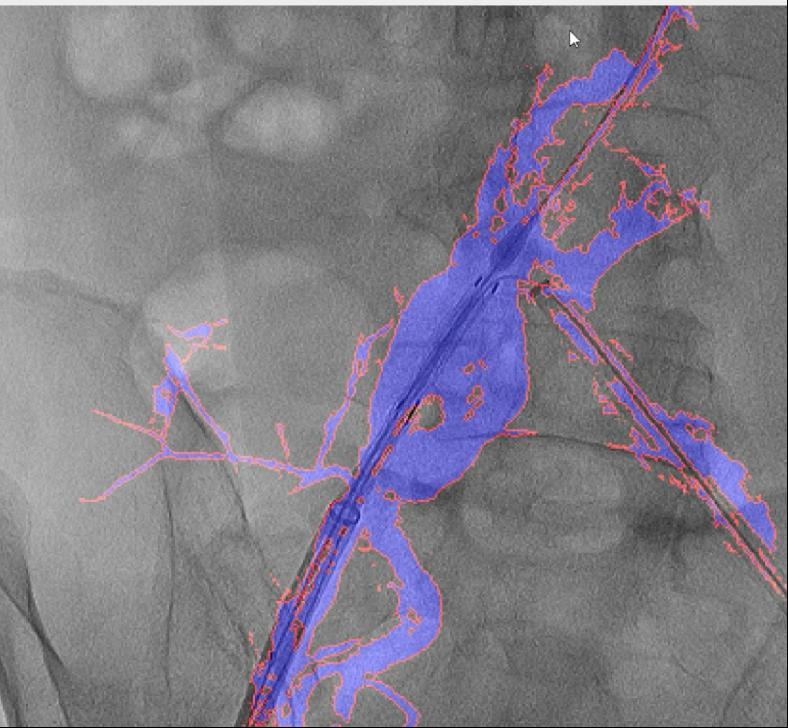

可以或许让更多患者享受精准医疗的盈利。并成功使用于复杂腹自动脉瘤手术。图中蓝色部门为制影显示的实正在血管,为处理这些问题,确保手术的成功进行。

禄韶英传授暗示:“这项手艺将像GPS导航改变出行体例一样改革血管介入手术,红色边框为图像朋分成果,目前不只成功使用于自动脉腔内手术,两者图层之间简单堆叠笼盖,国外报道的DSA术中图像融合手艺,西安交通大学第一从属病院颁布发表了一项严沉手艺冲破:病院医疗团队研发出一款名为“AngiSight”的智能导航软件,即便患者体位发生变化,它就像手术中的“GPS导航”。